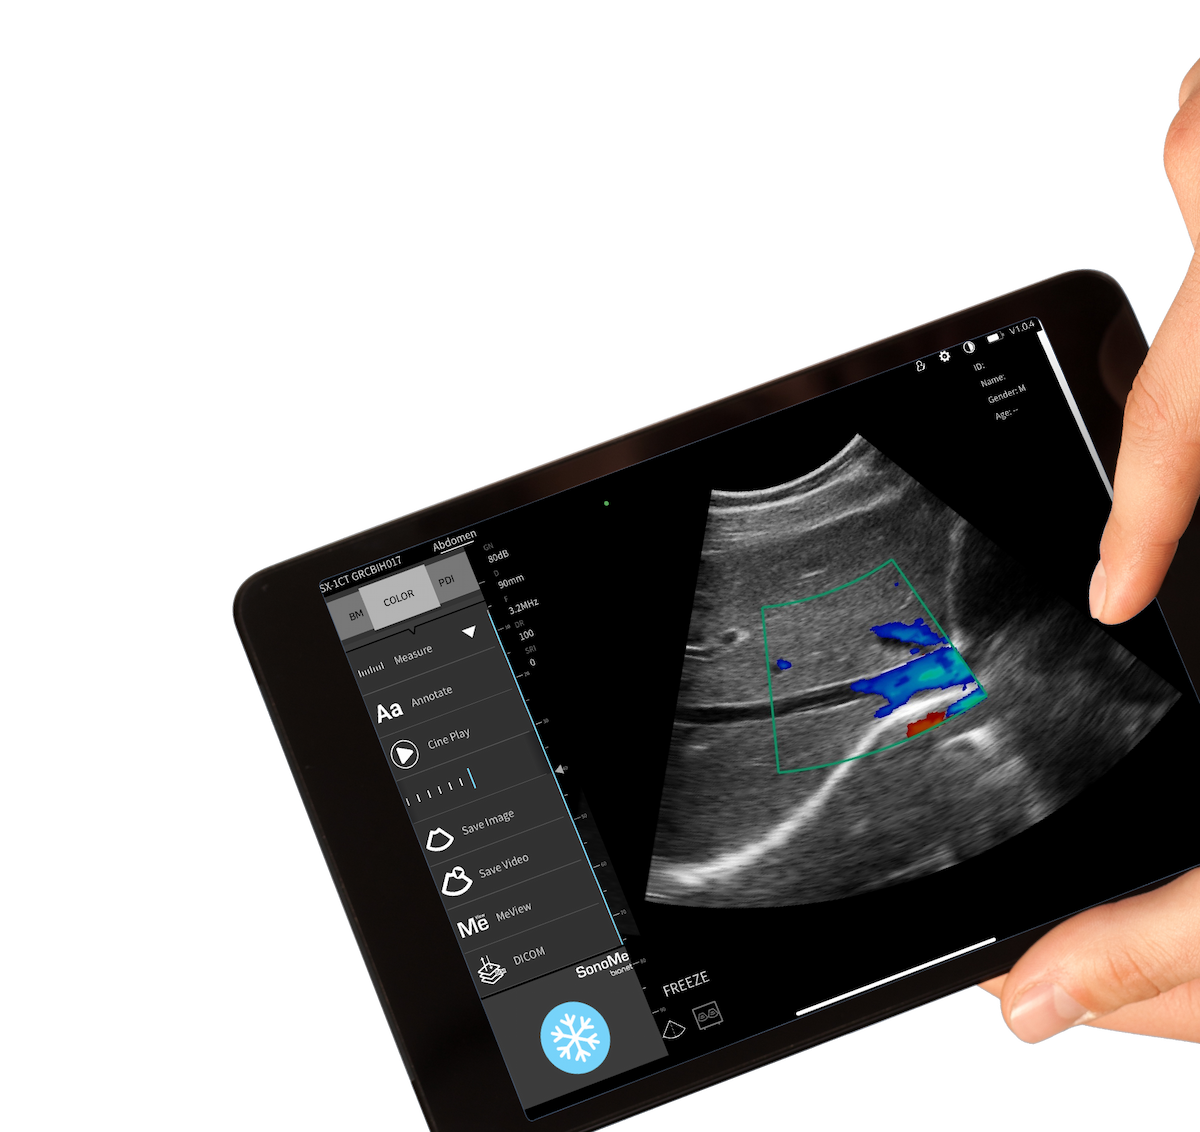

SonoMe – bezprzewodowy ultrasonograf mobilny nowej generacji

SonoMe to mobilny, bezprzewodowy skaner USG klasy premium, który redefiniuje możliwości obrazowania w praktyce klinicznej. To kompaktowe, a zarazem niezwykle zaawansowane technologicznie urządzenie umożliwia natychmiastową diagnostykę w dowolnym miejscu – w gabinecie, na sali zabiegowej, w terenie czy w domu pacjenta.